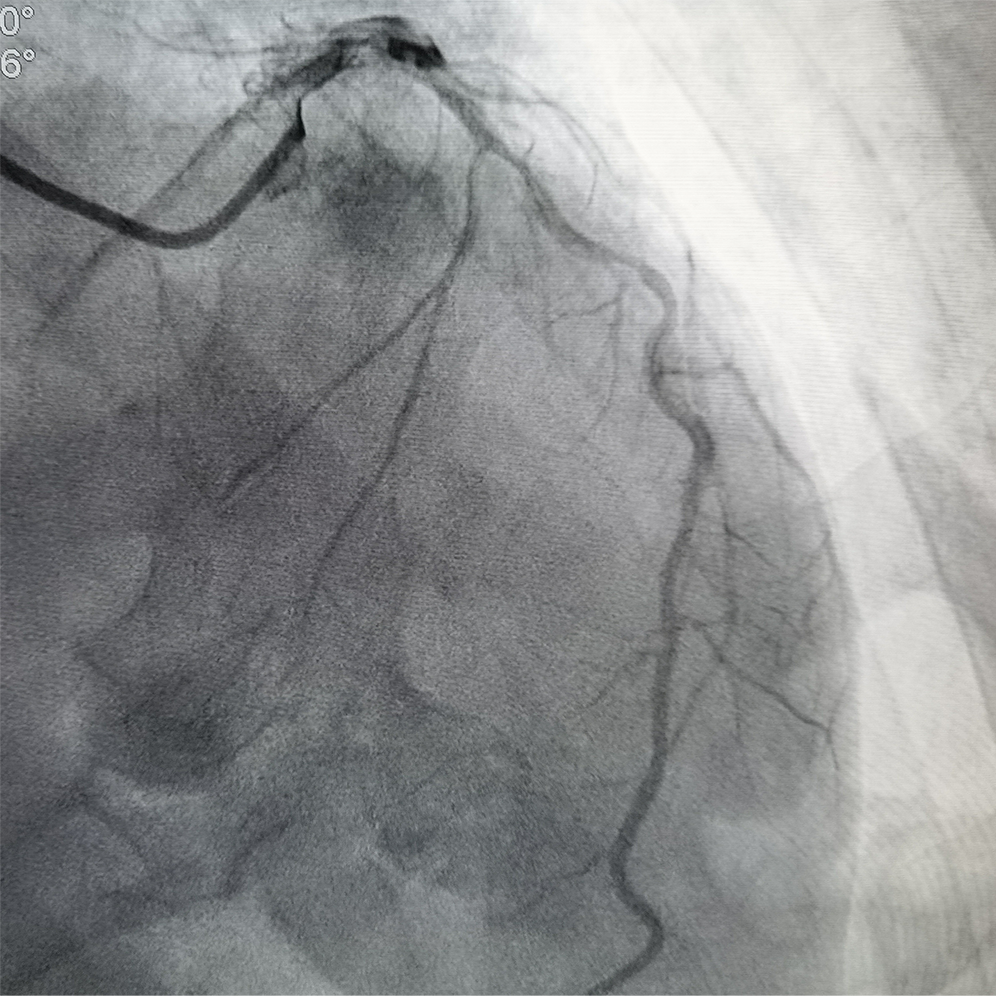

冠脉造影及IVUS检查提示前降支重度狭窄伴严重钙化

冲击波球囊处理冠脉钙化病变